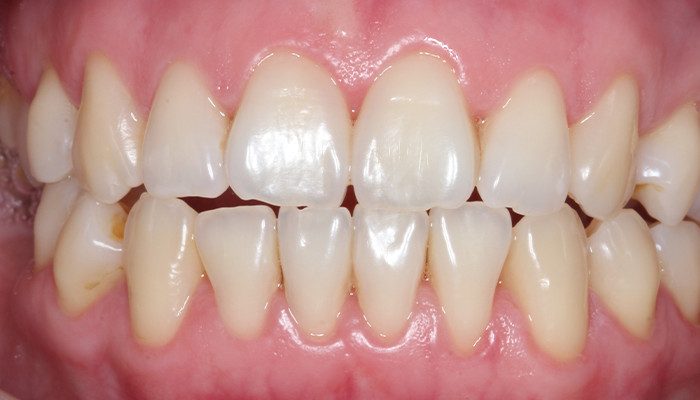

AVALIAÇÃO INICIAL

2 e 3 | Aspecto inicial intraoral.